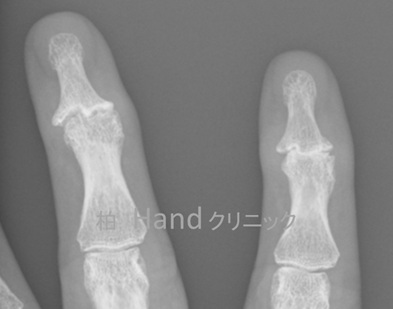

受診時のレントゲン写真

ものを持つ、つまむなどがつらく、ペットボトルも開けられなくなって受診した52歳女性のレントゲン写真。

画像提供:柏Handクリニック